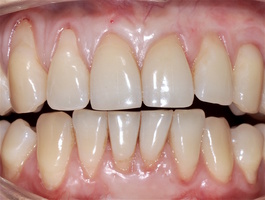

Во всех случаях применения аутотрансплантата и ТМО (dura mater) наблюдается сопоставимый положительный клинический результат по всем параметрам оценки рецессий десны (табл. 4). В случае нескольких зубов в области наиболее глубоких рецессий с наименьшими клиническими показателями имеет место сохранение класса рецессии не более первого класса (9 зубов) и глубиной не более 2 мм, 1.6 зуб — 3 мм.

В зарубежной литературе встречается также совокупный показатель эффективности лечения рецессий десны — процент закрытия корня зуба — отношение разница между конечным и исходным значениями глубины рецессии к исходному значению в процентах. Положительный результатом лечения является значение равное или более 80% [4]. Использование только показателя глубины рецессии десны для анализа эффективности лечения без учета остальных показателей (ТКД, ШКД, РРД, ЗДК) не дает полной картины результата и может быть применимо только в совокупности с другими показателями (рис. 6а-й).

Так в нашем случае процент закрытия корня зуба наблюдается больше 80% у 13 зубов. Менее 80% — у 11 зубов. Это связано с сохранением класса рецессии после лечения в области зубов с наибольшим классом рецессии и наибольшим показателем глубины рецессии. При этом средний показатель всех 24-х оперированных зубов — 83,1%. При этом среднее значение процента закрытия корня зуба для зубов с положительным результатом (более 80%) составляет 96,65%. Среднее значение для результатов менее 80% — 54,73, что связано с изменением глубины рецессий с 6 мм до 3 мм, с 4 мм до 2 мм и с 2 до 1 мм. При этом для аутотрансплантата и для ТМО результаты сопоставимы.

Через 12 месяцев (рис. 7а-г) на срезах компьютерной томограммы 11-ый и 13-ый зубы находятся в костной ткани, при этом костные пики и перегородки укрепились, объем их увеличился; вестибулярно заметен объем костной массы, предположительно компактной формации, исходя из электронной плотности участка. Этим объясняется отсутствие рецидива при лечении рецессии десны как в случае применения аутотрансплантата, также и ТМО (dura mater).